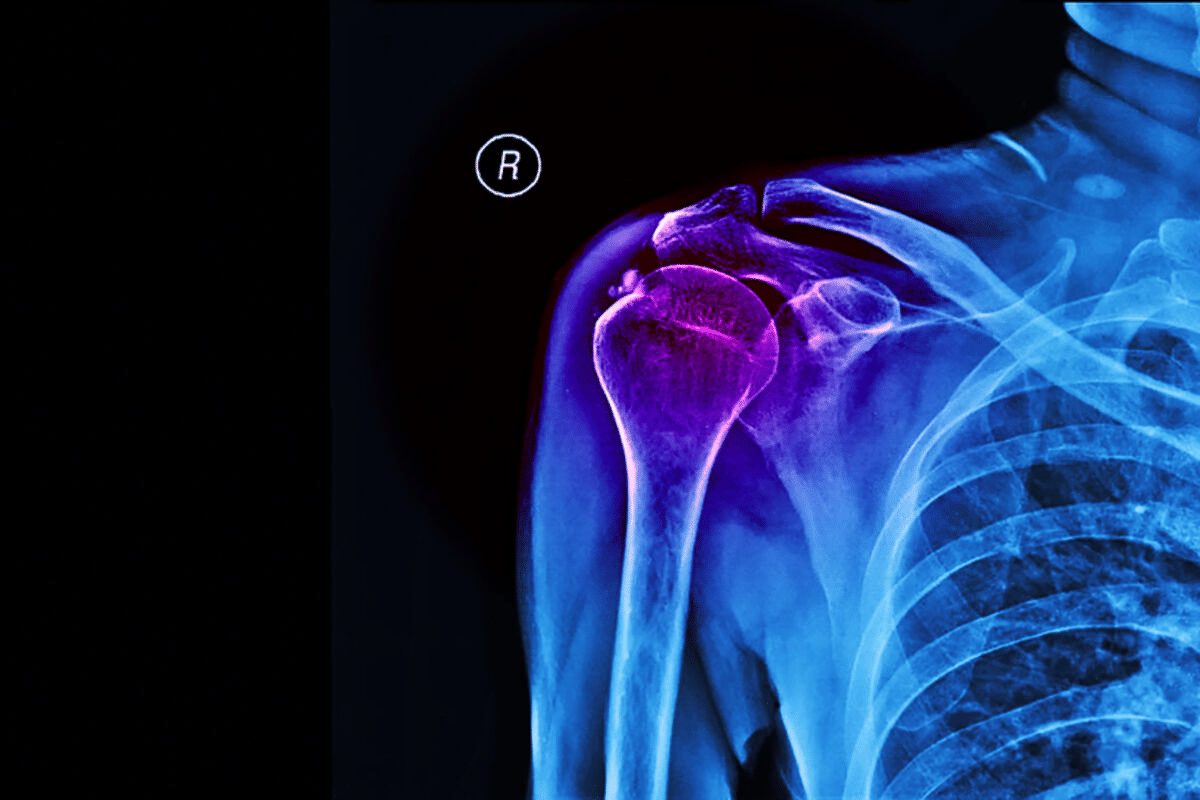

Valuable Rotator Cuff Exercises After Surgery: Full Guide

Recovering from shoulder surgery needs a well-thought-out exercise program. This program helps your shoulder heal in stages. At Liv Hospital, we know how important it is to get your shoulder back to normal. We use proven physiotherapy methods to help your shoulder heal right rotator cuff exercises after surgery.